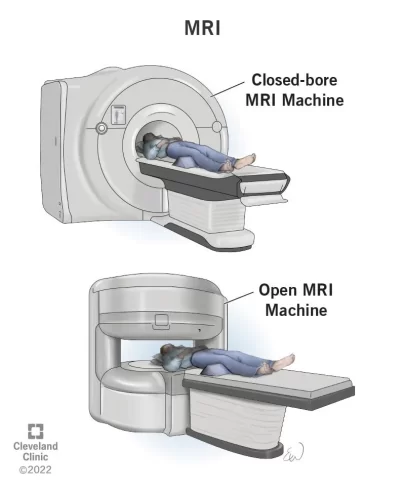

اسکن تصویر برداری رزونانس مغناطیسی (MRI یا Magnetic resonance imaging)

MRI با استفاده از امواج رادیویی و آهنرباهای قوی به جای اشعه ایکس، تصاویر دقیقی از بافتهای نرم بدن ایجاد میکند، بنابراین هیچ تشعشعی در کار نیست. ماده حاجب به نام گادولینیوم (gadolinium) اغلب قبل از اسکن به داخل ورید تزریق میشود تا جزئیات را بهتر ببینند.

MRI اغلب برای مشاهده دقیق تر توده استخوانی که در عکس اشعه ایکس دیده میشود انجام میشود. MRI معمولاً میتواند نشان دهد که توده احتمالاً تومور، عفونت یا نوعی آسیب استخوانی ناشی از علت دیگری است.

MRI همچنین میتواند به تعیین وسعت دقیق تومور کمک کند زیرا میتواند مغز استخوان را در داخل استخوانها و بافتهای نرم اطراف تومور، از جمله رگهای خونی و اعصاب مجاور را نشان دهد.

MRI همچنین میتواند تومورهای استخوانی کوچک را در چند اینچ دورتر از تومور اصلی (به نام متاستاز پرشی یا skip metastases) نشان دهد. دانستن وسعت استئوسارکوم هنگام برنامه ریزی برای جراحی بسیار مهم است. اسکن MRI معمولا جزئیات بهتری را نسبت به سی تی اسکن نشان میدهد (در زیر توضیح داده شده است).